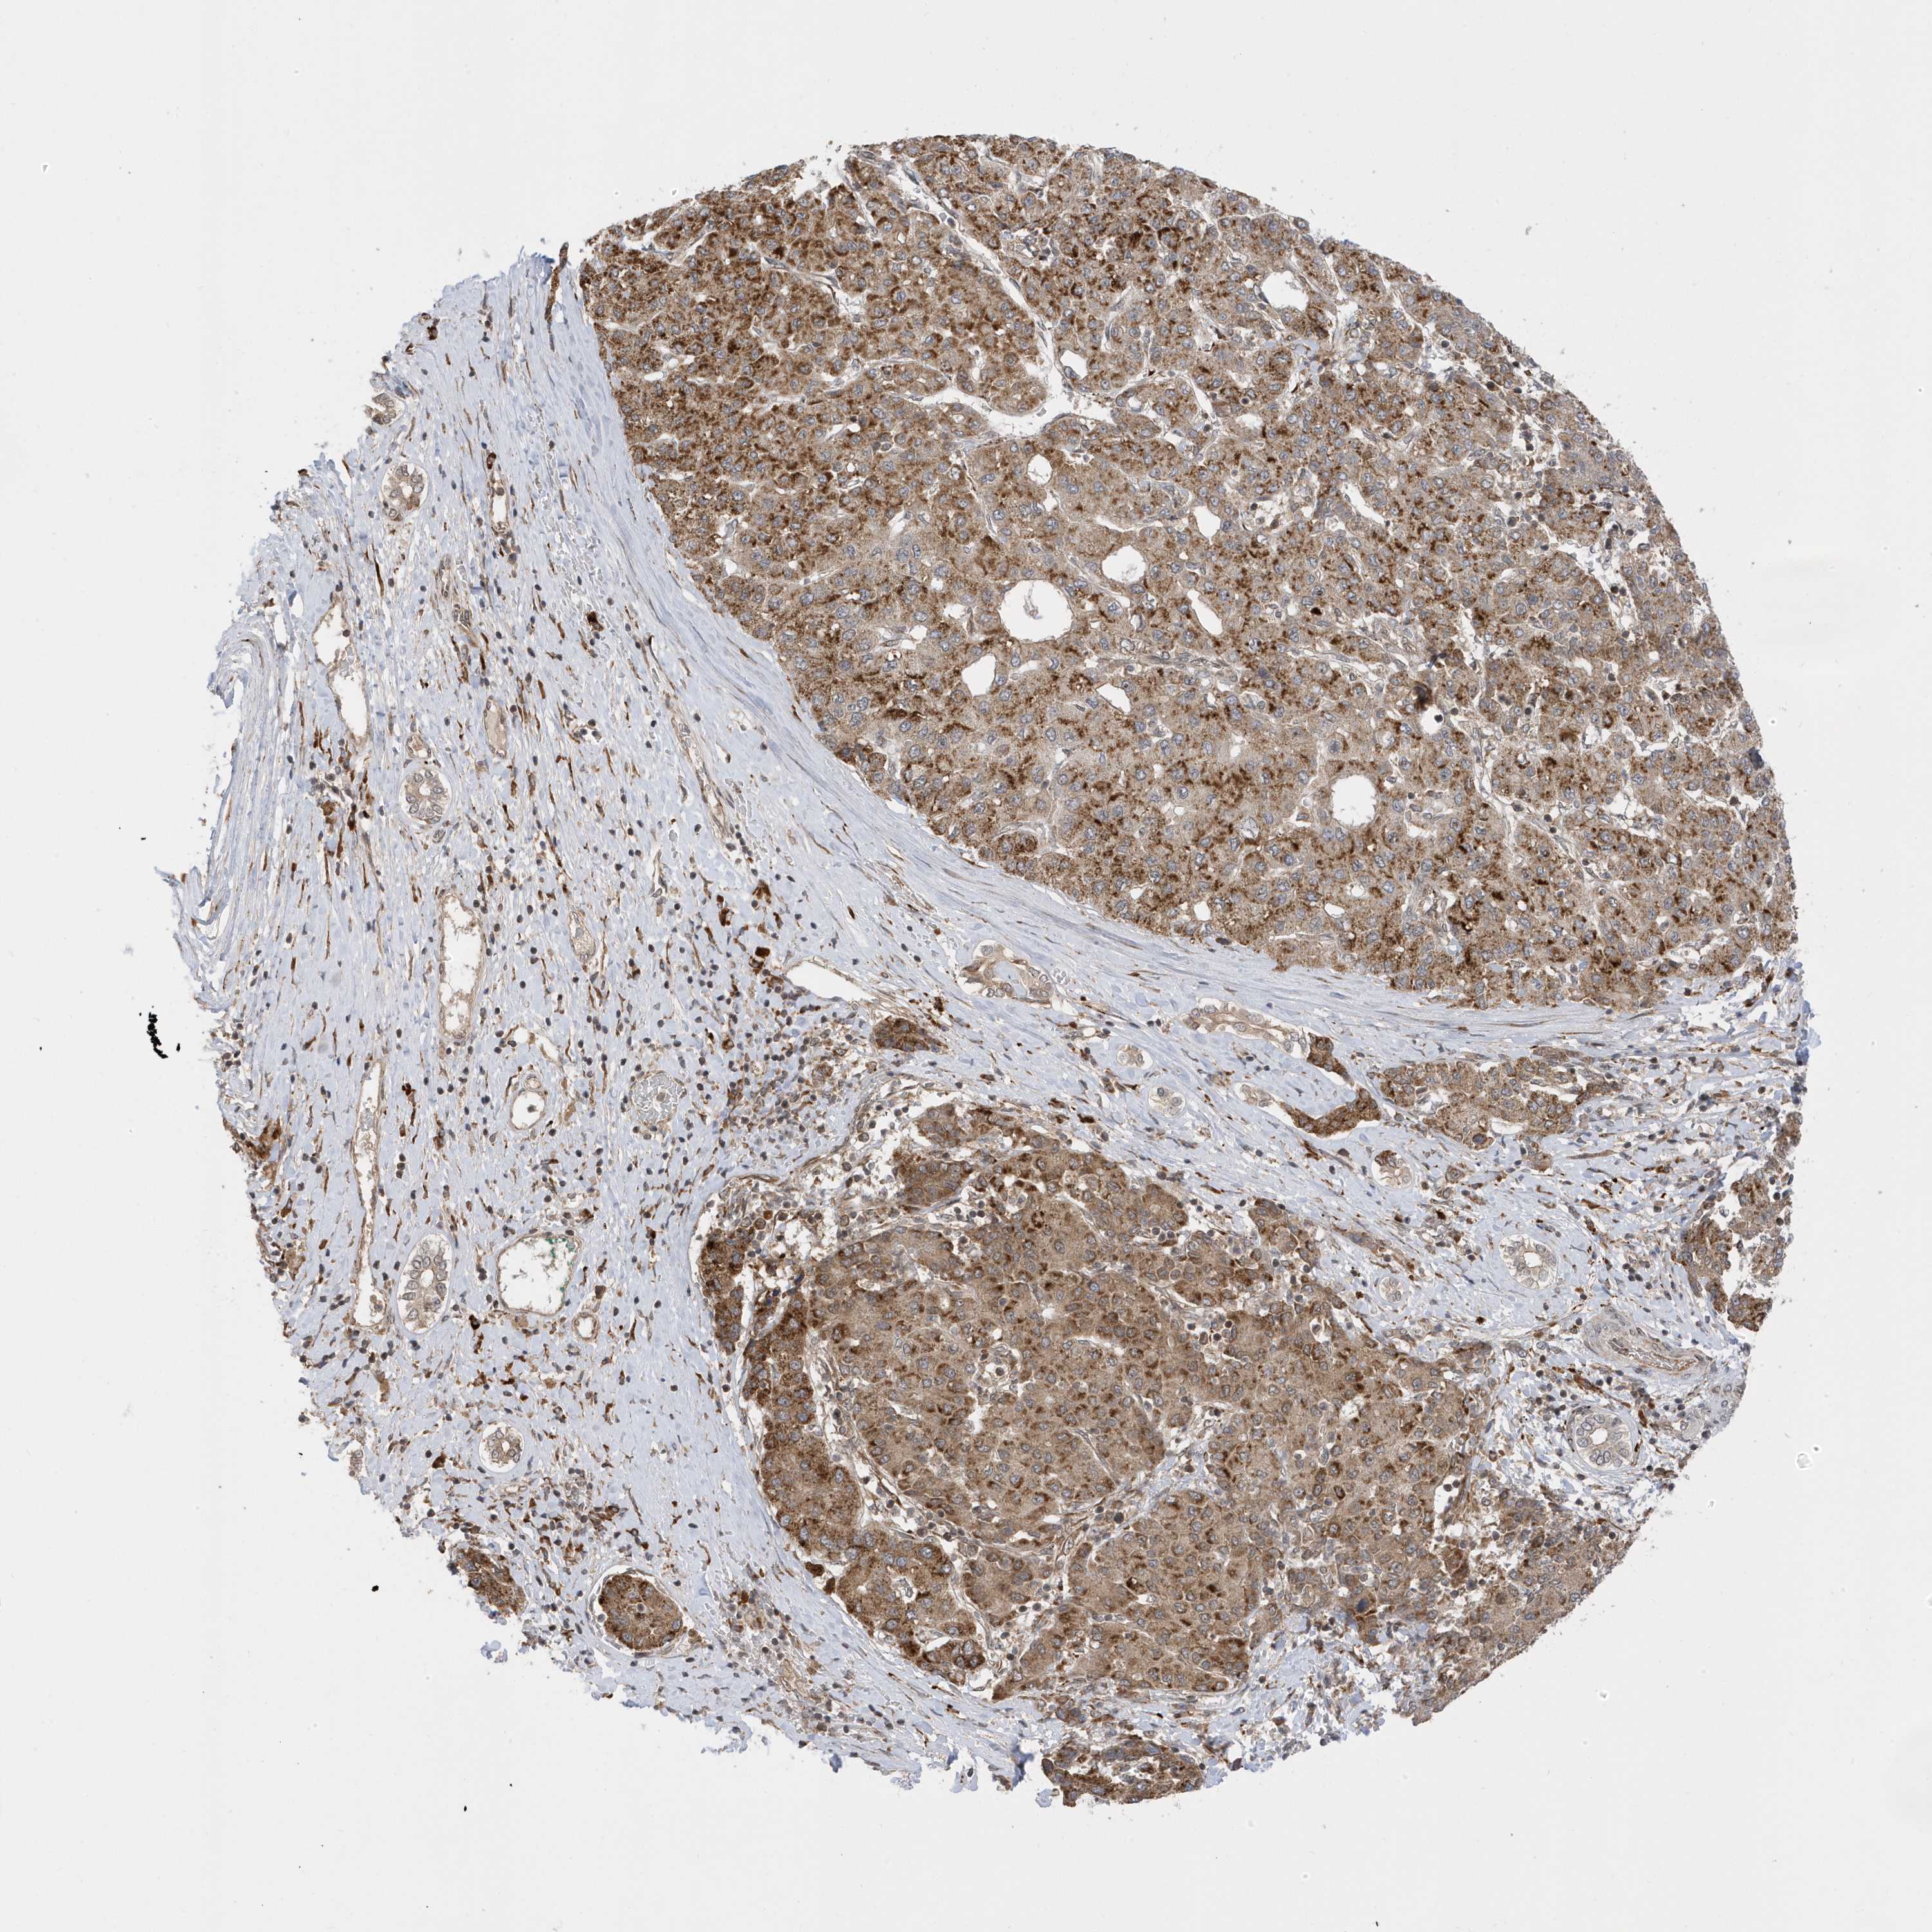

LIVER CANCER - Protein expressioni

A mouse-over function shows sample information and annotation data. Click on an image to view it in a full screen mode. Samples can be filtered based on level of antibody staining by selecting one or several of the following categories: high, medium, low and not detected. The assay and annotation is described here.

Note that samples used for immunohistochemistry by the Human Protein Atlas do not correspond to samples in the TCGA dataset.

Antibody stainingi

Antibody staining in the annotated cell types in the current human tissue is reported as not detected, low, medium, or high, based on conventional immunohistochemistry profiling in selected tissues. This score is based on the combination of the staining intensity and fraction of stained cells.

Each image is clickable and will lead to virtual microscopy that enables deeper exploration of all samples and also displays staining intensity scores, fraction scores and subcellular localization as well as patient and tissue information for each sample.

Antibody HPA034712

Staining

High

Medium

Low

Not detected

Intensity

Strong

Moderate

Weak

Negative

Quantity

>75%

75%-25%

<25%

None

Location

Nuclear

Cytoplasmic/membranous

Cytoplasmic/membranous,nuclear

Cholangiocarcinoma

Carcinoma, Hepatocellular, NOS